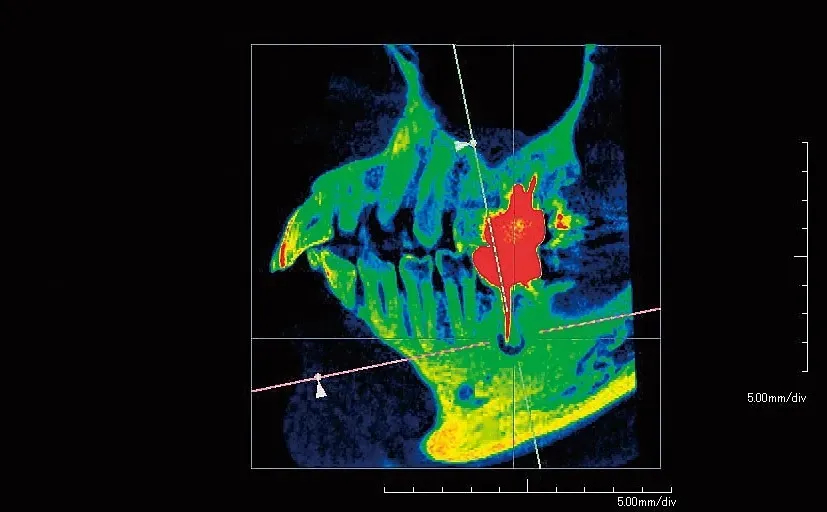

ファインキューブE2【アーム型X線CT診断装置】

ファインキューブのDNA、高画質・操作性の良さを引き継ぎ第2の進化を遂げ、より身近になったファインキューブ。新たにセファロ搭載機種もラインナップ。